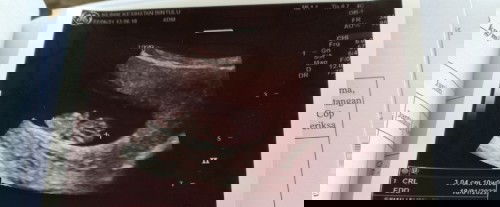

Hai Mommy semua, sya mengalami pendarahan sejak usia kandungan 20 minggu hingga skrg(24 minggu). Sya telah berjumpa dgn doktor . Spertinya tiada masalah apa2. Sbb baby dlm kandungan dlm keadaan baik. Pendarahan spoting saja . Berwarna gelap. Kdg ada warna merah dlam ketulan yg kecil. Adakah mommy pernah mengalami pekara sperti saya ini?#ingintahu #firstbaby